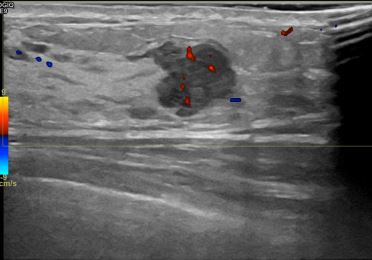

상기환자는 만져지는 멍울로  내원하신 40대초반

여성분으로 의심스러운 좌측혹 조직검사 시행해 침윤성암 으로 진단되었습니다